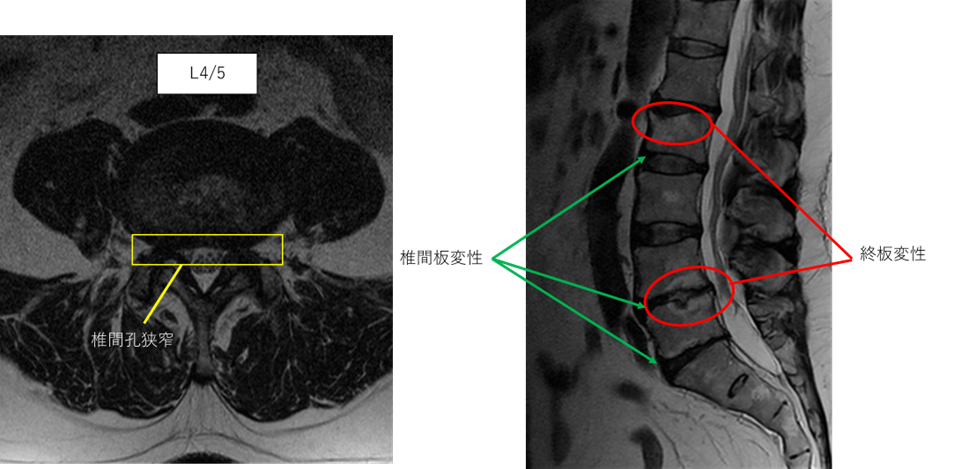

画像及び所見について

L1/2: 椎間板変性症、終板変性

L2/3: 異常なし

L3/4: 異常なし

L4/5: 椎間板変性症、両椎間孔狭窄、終板変性

L5/S: 椎間板変性症

以上の事が画像上認められます。

椎間板変性症、椎間孔狭窄、終板変性 を認め、主症状の原因の可能性が高い。